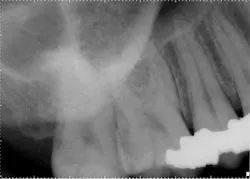

Exam: Teeth Nos. 2 through 5 responded normally to cold with no lingering and were asymptomatic to percussion, so the field of testing was expanded. Tooth No. 8 was nonresponsive to cold and heat. Both Nos. 7 and 8 were hypersensitive to percussion but had no restorative history, and the patient denied any history of trauma. There was no clinical evidence of an enamel defect associated with tooth No. 8. Radiographically, the apical and crestal bone was unremarkable around teeth Nos. 2 through 9. Teeth Nos. 3, 4, and 5 had significant restorative histories.Anterior preop

Treatment options: Root canal treatment No. 8, no treatment, or extraction. The patient was certain tooth No. 3 was the culprit, and No. 8 had no restorative or trauma history. As a result, waiting for symptoms to localize was a consideration. However, the patient experienced significant relief following administration of local anesthetic around tooth No. 8, and a root canal was completed.Posterior right

Treatment: Upon access, a necrotic pulp was identified. The dentin triangle was removed with a series of Gates-Glidden burs. Copious irrigation was completed with sodium hypochlorite. The canal was instrumented with stainless steel hand files and rotary ProFile series 29, both 0.04 and 0.06 taper. The canal was filled with a warm vertical downpack and thermoplasticized gutta-percha backfill. To maximize esthetics, the space was underfilled to the level of the crestal bone to prevent staining the chamber.